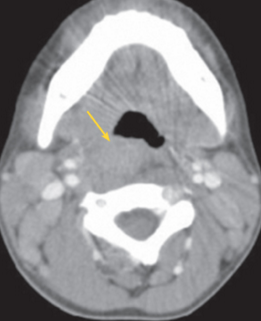

Eric Peeples, MD; Anthony Yaghmour, MD; Archana Chatterjee, MD, PhD; Meera Varman, MD

<p>A 4-year-old Latino boy with mosaic Turner syndrome (45,XY/45,XO) presented with fever, temperature up to 40.5ºC (105ºF), of 3 days’ duration. He also had swelling on the right side...